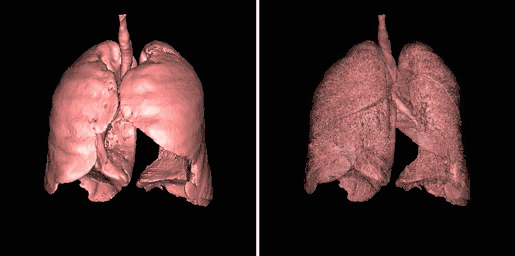

- An opacity table can be applied to the results so that surfaces from internal features can also be visualized, as illustrated in Figure 5.31. Here, axial CT data from the patient's airways have been segmented using a region growth technique and the result processed using surface rendering, with full opacity as shown in the left panel and with a reduced opacity (30%) as shown in the right panel:

- Notice that internal features of each lung can be discerned when the opacity is reduced. Notice also that continued viewing of this type of transparency display can generate apparent reversal of the image rotation, similar to that noted for the 3D MIPs above. One method of overcoming this type of problem is to segment each lung, for instance. and to blend the results, as illustrated in Figure 5.32.